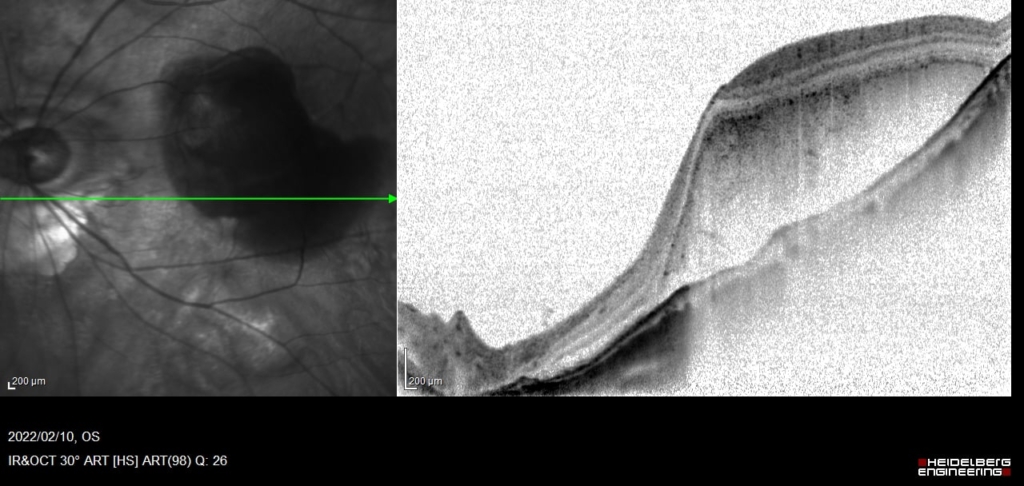

間隙は縮小しているが、PED全体は増大している。

硝子体注射2日後に出血

CNVの活動性の指標として、PED内部のCNVとBruch膜に間にBruch膜を後方に押すように生じる間隙や、PED自体の増大は注意が必要。